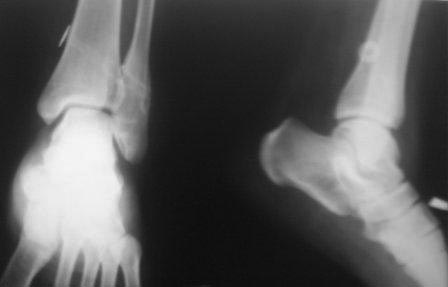

Обратилась  К.19 лет. Со слов матери 10-12 лет назад получила

перелом лодыжек, лечилась консервативно, ч-з год повторно получила

травму г/стопного сустава, лечилась консервативно. С тех пор беспокоят

периодические боли, отеки, слегка прихрамивает. Неоднократно лечились

амб и стац, в разных отделениях. 1,5 год назад в одной б-це произведена

операция фиксация дистального м/б синдесмоза болт -стяжкой , и через год

удалена   м/конструкция  и  вся клиника повторилось. Девочка

упитанная, . Мне кажется  у б-ной был чрезсиндесмозный  оскольчатый

перелом м/б кости с разрывом переднего отд.синдесмоза, (44В1.3).

неправильное сращение и укорочение м/б кости, или даже с поворотом. , за

счет этого хр.неустойчивость дистального межберцового синдесмоза. И к

тому болт–стяжка проведена  неправильно,с нарушением техники и результат- 0.

Предварительно думаем: косая надсиндесмозная остеотомия м/б кости,

удлинение и адаптация мед.суставной поверхности наружной лодыжки,

фиксация 1/3 трубчатой пластиной, ревизия  дистального синдесмоза,

возможно пластика синдесмоза(пока незнаю чем) , и две позиционного

винта, или болт–стяжка.  Еще будем глубже заниматься, КТ не работает,

МРТ  есть.